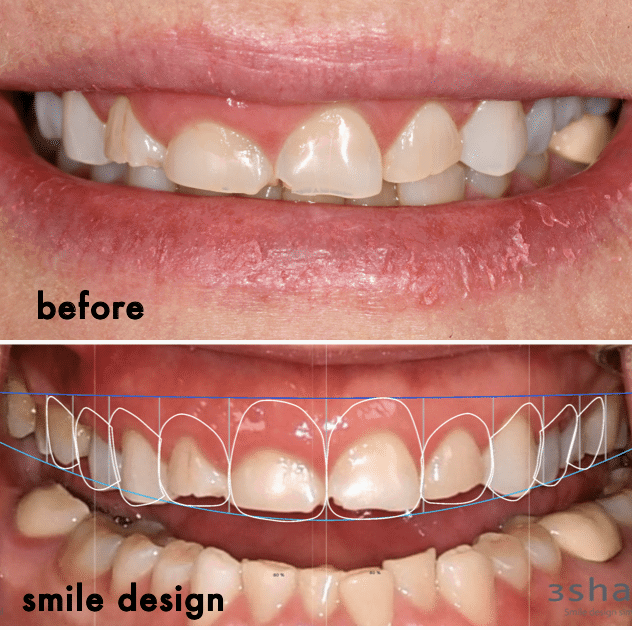

Digital Smile Designing

Digital smile design is a digital treatment planning tool that enhances diagnostic vision and improves predictability which helps to create beautiful smiles. With this we can plan treatment more effectively as a team, and perform better treatments in a more efficient way.